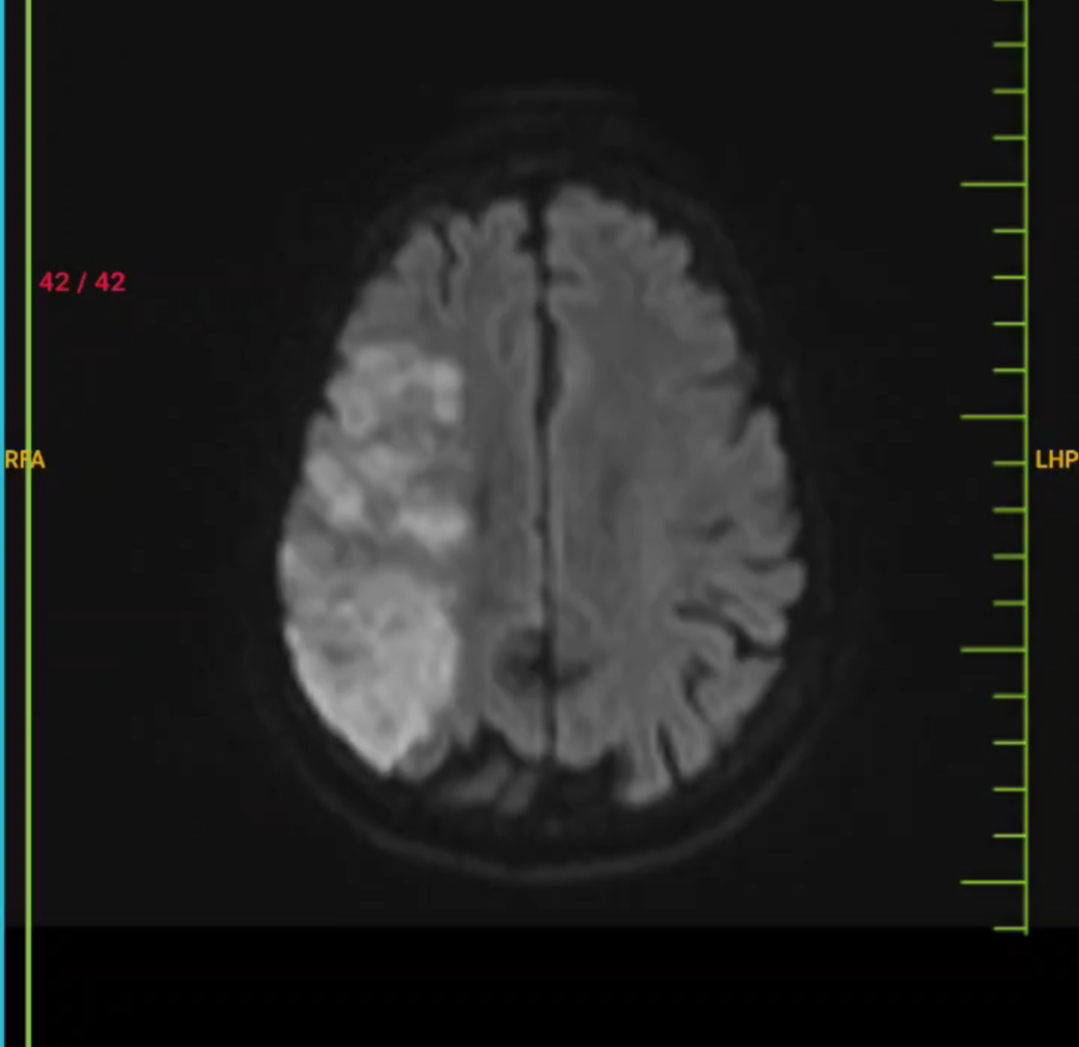

Rt CVA with left hemiplegia with global aphasia

Right sided CerebroVascular Accident with left sided Hemiplegia with involvement of area supplied by middle cerebral artery due to embolism .